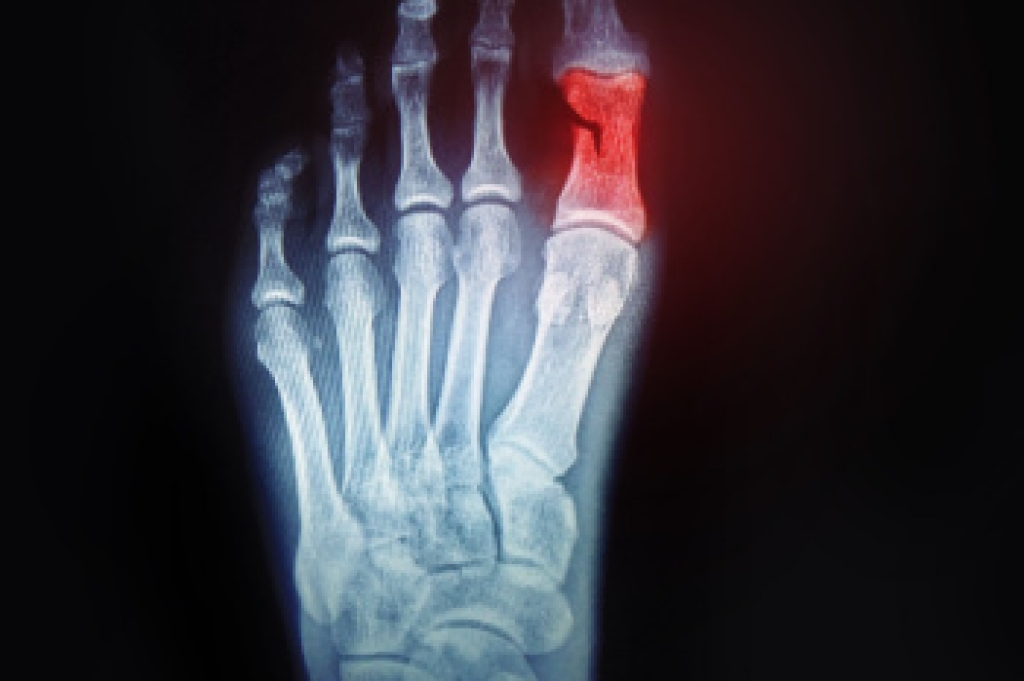

Broken Pinky Toes and Proper Care

A broken toe occurs when one of the toe bones fractures due to trauma, stubbing, or dropping a heavy object on it. Causes include sports injuries, accidents, or repetitive stress. Risk factors are osteoporosis, poor footwear, and high impact activities. Symptoms may include swelling, bruising, and difficulty walking. Taping can help stabilize the toe if the break is minor, determined by evaluating pain, alignment, and mobility. The process involves gently wrapping the injured toe to its neighbor for support while avoiding circulation issues. A podiatrist can confirm the diagnosis, and provide treatment, which may or may not include buddy taping. If you suspect you have broken your pinky toe, it is strongly suggested that you promptly consult a podiatrist who can accurately diagnose the injury and offer the best treatment solution, preventing long-term complications.

What to Know About a Broken Toe

Although most people try to avoid foot trauma such as banging, stubbing, or dropping heavy objects on their feet, the unfortunate fact is that it is a common occurrence. Given the fact that toes are positioned in front of the feet, they typically sustain the brunt of such trauma. When trauma occurs to a toe, the result can be a painful break (fracture).

Symptoms of a Broken Toe

- Throbbing pain

- Swelling

- Bruising on the skin and toenail

- The inability to move the toe

- Toe appears crooked or disfigured

- Tingling or numbness in the toe

Generally, it is best to stay off of the injured toe with the affected foot elevated.

Severe toe fractures may be treated with a splint, cast, and in some cases, minor surgery. Due to its position and the pressure it endures with daily activity, future complications can occur if the big toe is not properly treated.